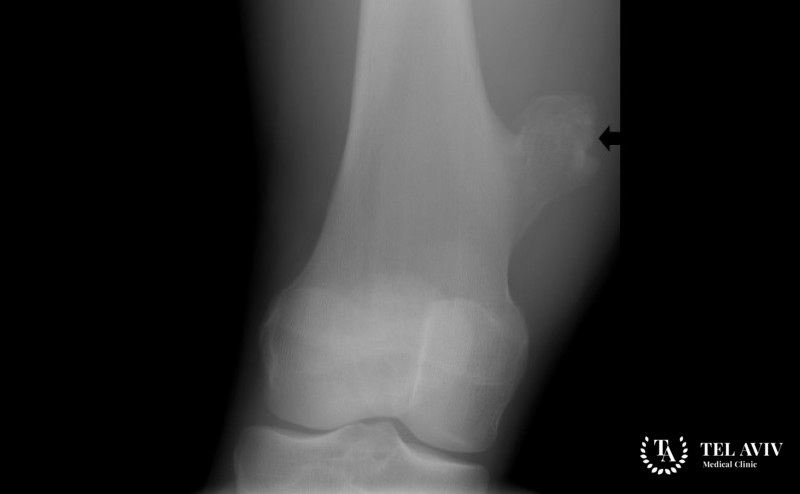

Для постановки правильного диагноза, от которого будет зависеть выбор лечения, проводится тщательный анализ полученной информации после проведения лабораторных и инструментальных исследований. Необходимо не просто установить наличие хрящевой неоплазии, но и определить ее структуру, размеры, стадию развития, провести дифференциальную диагностику. В клинике Tel Aviv Medical Clinic для получения максимально точного результата применяется передовое оборудование, позволяющее использовать такие методы диагностики:

- Рентгенография.